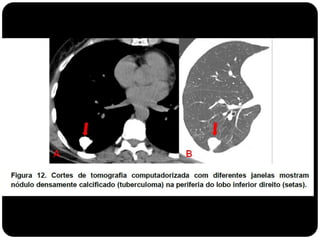

Pequeno nódulo no pulmão direito

Nódulos

 O nódulo pulmonar é uma lesão arredondada ou ovalada, de

limites parcialmente precisos, com menos de 3 cm de

diâmetro.

Granuloma deTB